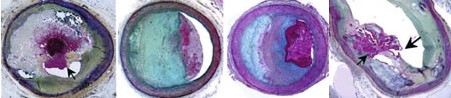

组图所示为动脉粥样硬化病变破裂,管腔血栓形成。自左向右依次为:斑块破裂、斑块蚀损、钙化结节